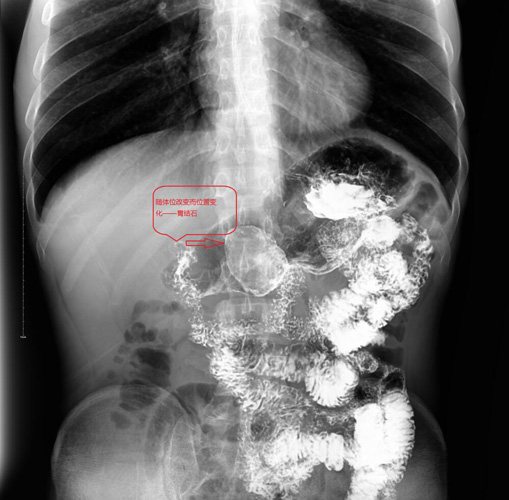

随着体位的改变,钡剂均匀涂抹于胃腔,见胃腔内形成一个类圆形充盈缺损影像,病灶开始露出面目。同时胃腔的充盈缺损影像有多种可能,例如大家最熟悉的肿瘤,那么该如何区分呢?转动体位,有助于鉴别是长在胃壁上固定的肿瘤还是胃腔内可移动的其它东西。

患者做一些翻滚动作后,又加之胃腔内钡剂的排空减少,摄片见刚才的充盈缺损影,变成一枚有薄壳一般类圆形影,如鸡蛋般大小,并随着患者体位的改变而发生位置的变化,这就基本可以肯定它就是真凶:胃结石!